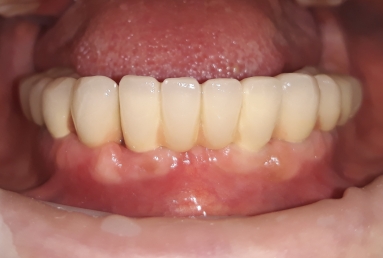

Our patient suffered from advanced periodontitis and we had to extract all mandibular teeth. After 2 month we inserted 8 Alpha Bio implants that healed in 4 months. All this time a full mobile temporary prosthesis was made, that was replaced in the end with fixed restorations made of porcelain fused to metal.

In the next step, tha patient wants to replace also the maxilary old mobile prosthesis with a fixed restoration.